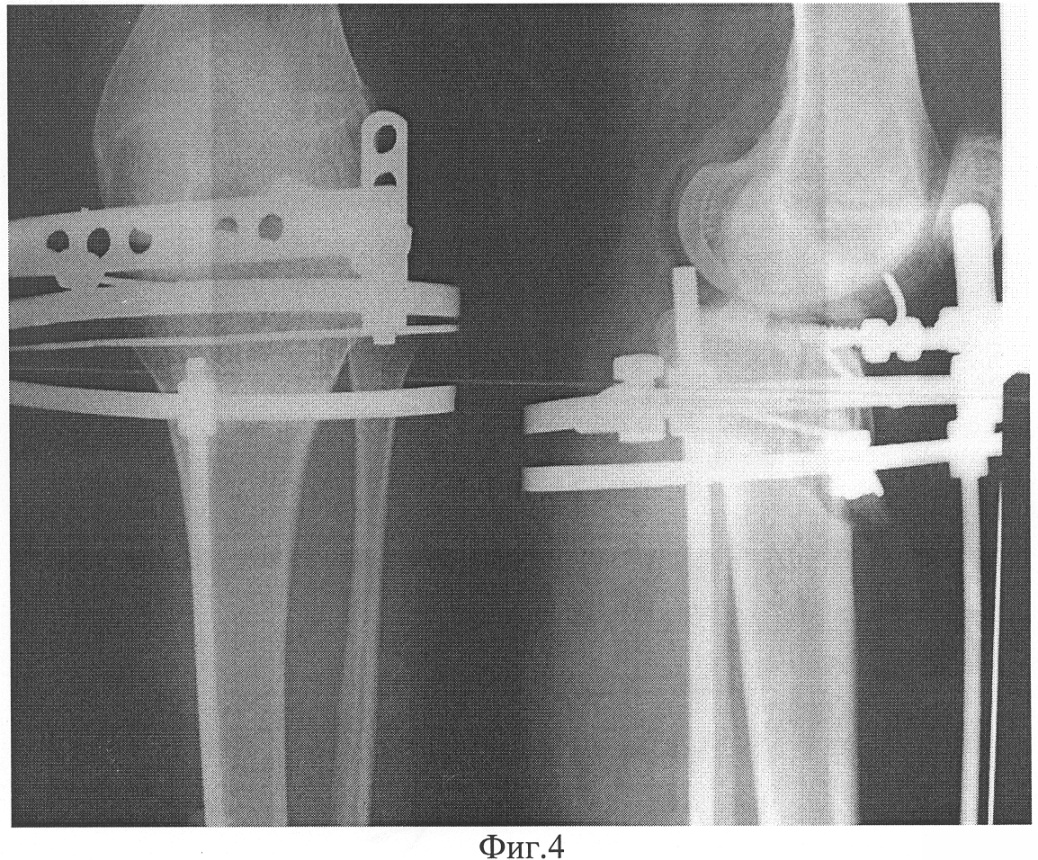

Фиг.2 – прямая проекция (вид спереди) до лечения;

На рентгенограмме левой конечности в прямой проекции (фиг.2) зафиксировано сужение и асимметрия суставной щели: полное ее отсутствие по наружнолатеральному углублению и умеренное сужение с внутреннемедиальной верхней суставной поверхности большеберцовой кости, что свидетельствует о вальгусном искривлении коленного сустава и отклонении центра голени от механической оси нижней конечности. В субхондральной зоне большеберцовой кости отмечены признаки дистрофических изменений костной структуры, что является проявлением дефицита хрящевого покрытия проксимального мыщелка большеберцовой в заднемедиальном направлении.

Диагноз: подвывих левой голени кзади, рекурвационно-вальгусная деформация левой нижней конечности на уровне коленного сустава. Максимальный дефицит суставного покрытия проксимального конца большеберцовой кости в сагиттальной плоскости – 8 мм.